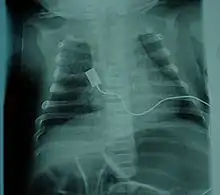

![]() | |

| Location of neurons affected by spinal muscular atrophy in the spinal cord | |